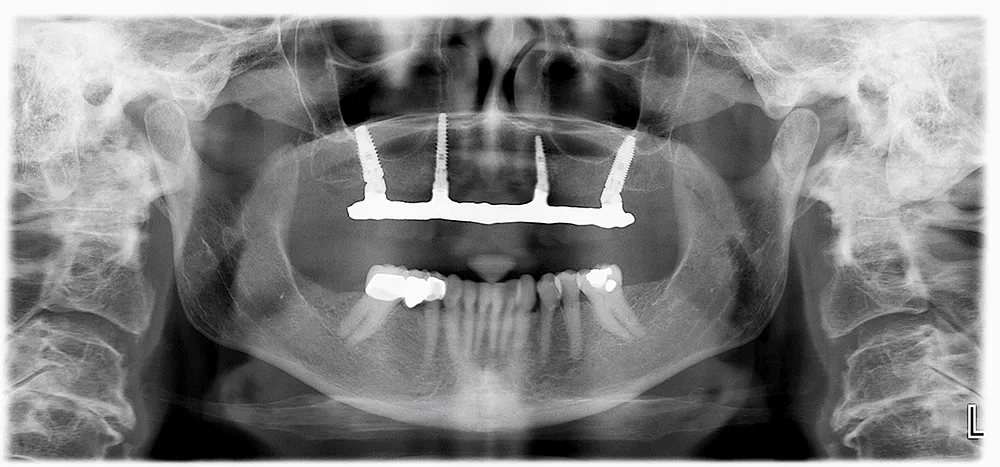

전체 임플란트는 위아래 각각 14개씩 28개의 치아가 있으며 14개의 치아 모두 상실된 경우 14개의 임플란트를 모두 식립하는 것이 아니라 8~10개의 임플란트를 식립 후 머리 부분의 치아를 연결하는 방식입니다.

즉, 여러 개의 인공 치아 뿌리(임플란트)를 잇몸과 턱뼈에 식립하여, 그 위에 고정식 틀니나 브릿지를 장착하는 치과 치료 방법입니다. 이는 주로 전체 치아가 상실된 환자들에게 적용되며, 부분적인 치아 상실을 보완하는 부분 임플란트와 구분됩니다.